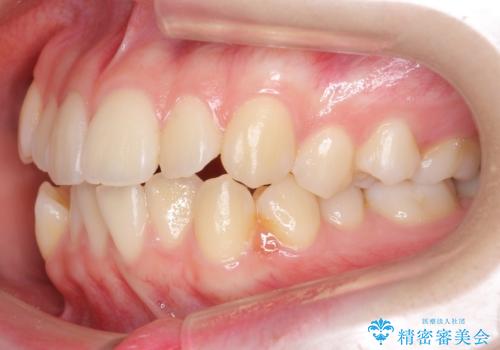

下の八重歯 歯を抜かずに インビザライン治療

- 歯並びのがたつきを主訴に来院。

抜歯してワイヤー矯正という選択肢も提案しましたが、マウスピース矯正で、歯を抜かずに並べてほしいとのことでした。

スペースを確保するために、歯をわずかに削る処置、奥歯を後ろに下げる処置(インプラント矯正)を行っています。